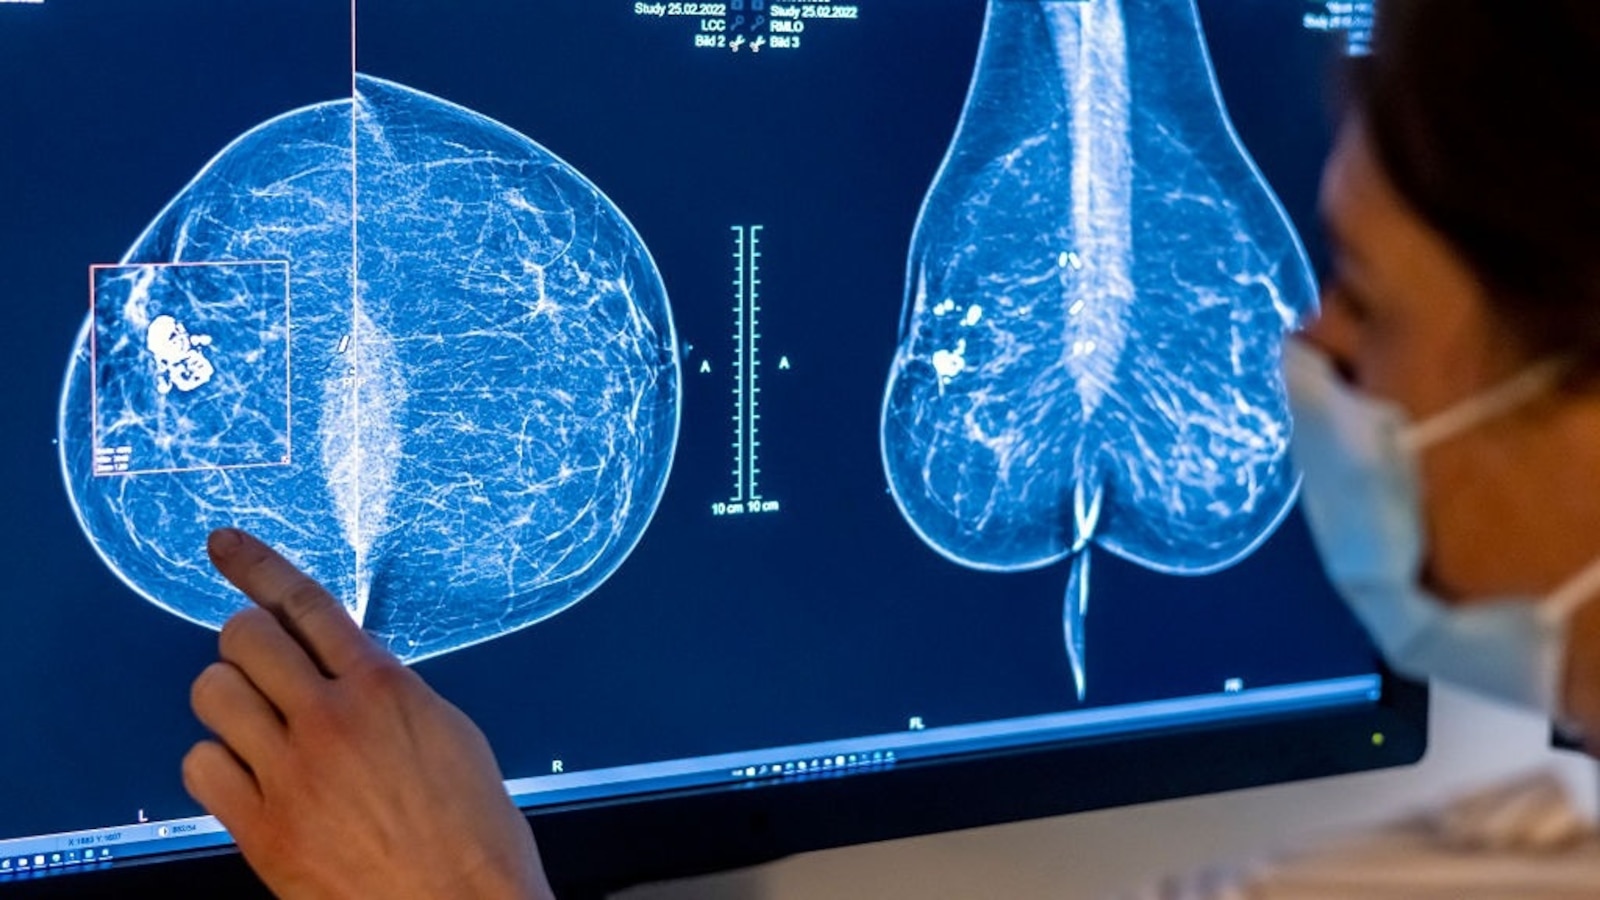

Medical personnel use a mammogram to look at a girl’s breast for breast most cancers. Photograph: Hannibal Hanschke/dpa

Image Alliance/dpa/image alliance by way of Getty I